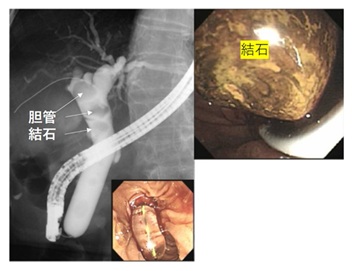

乳頭を太いバルーンで拡張(写真左)、大きな結石を取り出した(写真右)。